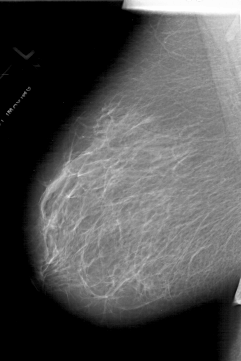

A_1717_1.LEFT_MLO

LEFT_MLO LINES 6136 PIXELS_PER_LINE 4096 BITS_PER_PIXEL 12 RESOLUTION 43.5 NON_OVERLAY